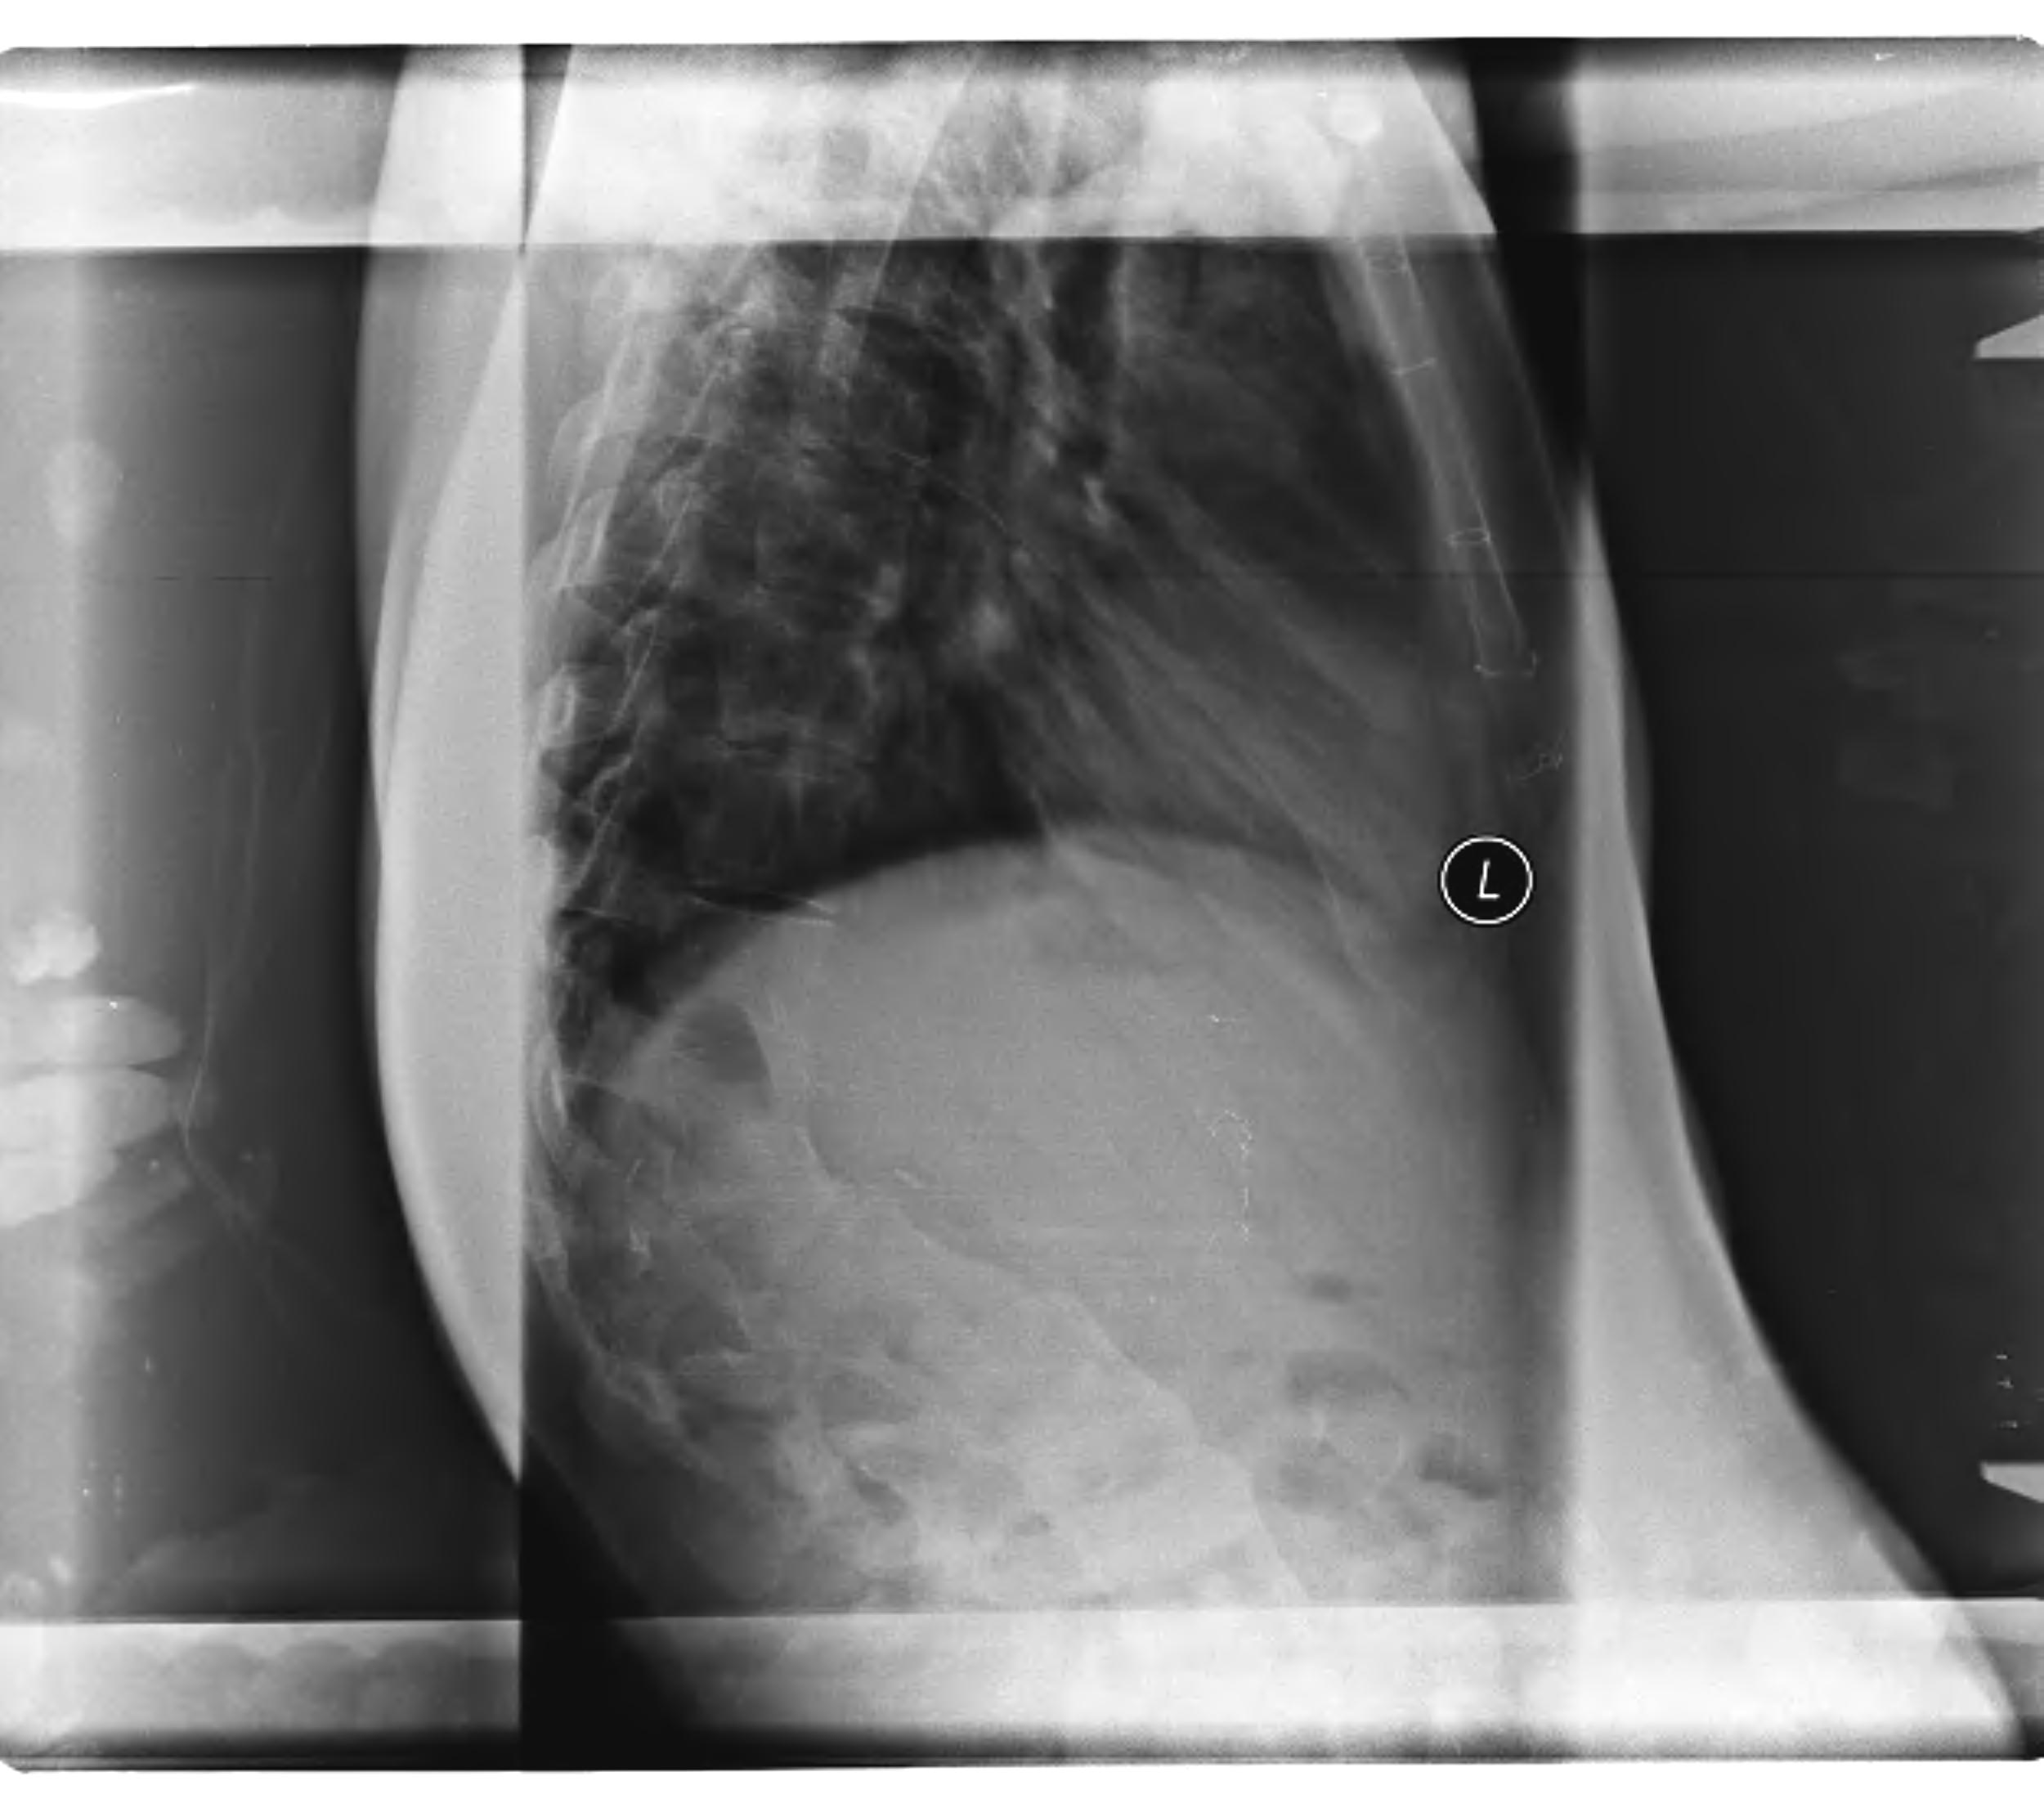

Kyphosis due to congenitally anomalous vertebrae

- characterized by severe angular deformity

- prominent gibbus at the apex of the curve

Deformity can become very severe (Type I)

- breakdown of the overlying soft tissues

- compression of abdominal viscera

- impairment of pulmonary function